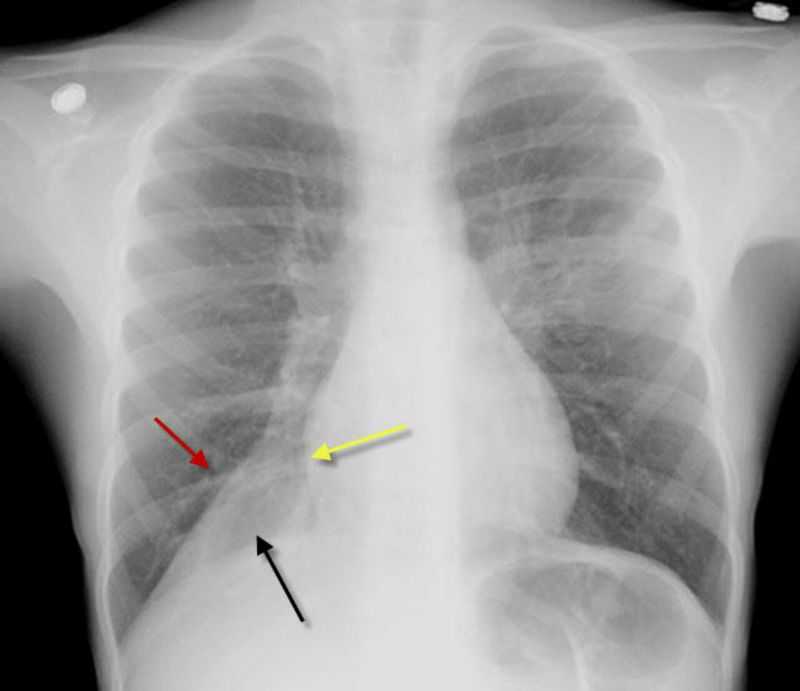

CXR shows Right Lower Lobe (RLL) Atelectasis In this graphy there is a triangular or wedge-shaped density at the right lung base medially (black arrow) that displaces the major fissure inferiorly (red arrow), obscures the right hemidiaphragm and maintains the shadow of the right heart border (yellow arrow).